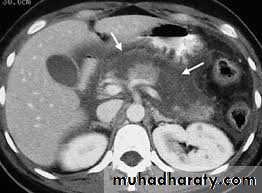

Pancreatic calcifications

CT scan in chronic pancreatitis

ERCP finding in chronic pancreatitis